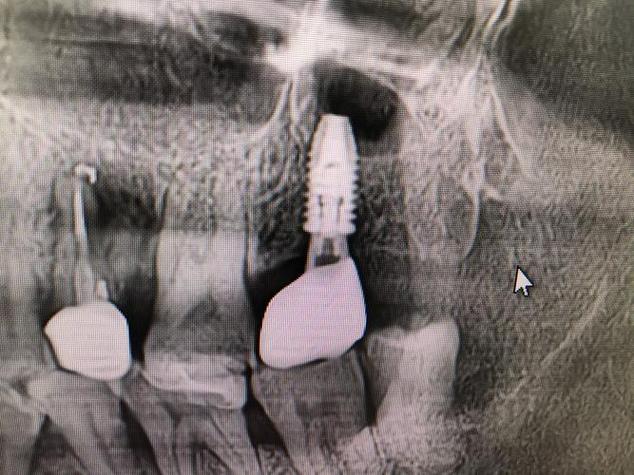

- 影像学检查:拍摄口腔曲面断层片或CBCT(锥形束CT),评估牙槽骨的高度、宽度、密度,以及邻牙、神经管(如下牙槽神经管)、上颌窦的位置,避免术中损伤重要结构。

- 缝合牙龈,术后拍摄X光片确认种植体位置。